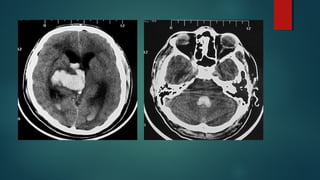

Este documento es el programa para un taller de imágenes del curso de emergencia 2015 impartido por el Dr. Víctor Delgado. El taller se centra en el uso de imágenes médicas para el diagnóstico y tratamiento de pacientes en coma traumático según la base de datos de Marshall. El Dr. Delgado es el único instructor repetido a lo largo del documento.